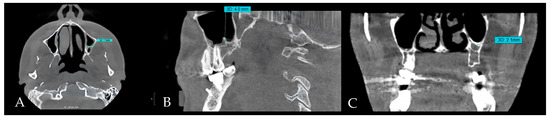

Assessment of the Sinus Septa Using CBCT: A Cross-Sectional Study in the Asir-Region Population, Abha Residents

by Hassan Ahmed Assiri, Atheer Almuaddi, Reema Malwi, Norah Alwadai, Ali Azhar Dawasaz, Abdullah Alqarni and Saeed Alassiri

J. Clin. Med. 2025, 14(24), 8784; https://doi.org/10.3390/jcm14248784 - 11 Dec 2025

Background: Anatomical variations of the maxillary sinus, including the septa, can affect surgical outcomes. This study aimed to present the characteristics of maxillary sinus septa in an Asir-region cohort using cone-beam computed tomography (CBCT). Methods: Archival adult CBCT scans of patients [...] Read more.

Background: Anatomical variations of the maxillary sinus, including the septa, can affect surgical outcomes. This study aimed to present the characteristics of maxillary sinus septa in an Asir-region cohort using cone-beam computed tomography (CBCT). Methods: Archival adult CBCT scans of patients at the King Khalid University College of Dentistry were reviewed in this retrospective cross-sectional study. Septa were measured in axial, coronal, and sagittal planes and classified as vertical, oblique, or horizontal. Correlations between the characteristics of the septa and both age and sex were analyzed. Results: Of the 400 CBCTs randomly selected between May–August 2025, 350 were suitable for analysis; among them, only 26 patients (53.8% male; age, <30 years) presented with sinus septa. The septa were unilateral in 16 (61.5%) and bilateral in 10 (38.5%) patients, without any significant differences based on sex (χ2 = 0.248; p = 0.619) or age (χ2 = 5.491; p = 0.139). Oblique and horizontal orientations were most common on the right (n = 10) and left (n = 11) sides, respectively; no associations were observed with sex (p > 0.05). The mean mediolateral length and septal height ranged from 7.8 to 10.3 mm and ~8.2 to 8.5 mm, with no sex- or age-related differences. Septal thickness did not vary by age (p > 0.05). Pathologic mucosal findings were infrequent and showed no association with septal location or side. Conclusions: These findings provide region-specific data on maxillary sinus septa in the Asir-region cohort, contributing to the understanding of anatomical variations before planning surgical interventions. Full article

Show Figures

Figure 1